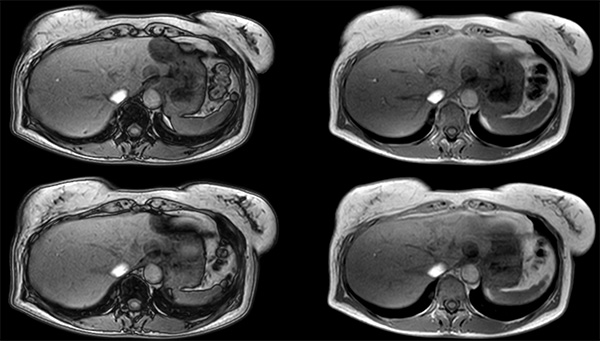

Patient with multiple liver lesions showing up hyperintense on T2-weighted images. The high spatial resolution of MultiVane XD can be appreciated by comparing the images demonstrating the two hyperintense focal liver lesions. mDIXON Quant was performed for quantification of intralesional and hepatic parenchymal fat content. The fat content in the liver parenchyma was normal. The lesion has a fat fraction of 25-30%. Histopathologic diagnosis was hepatocellular adenoma.